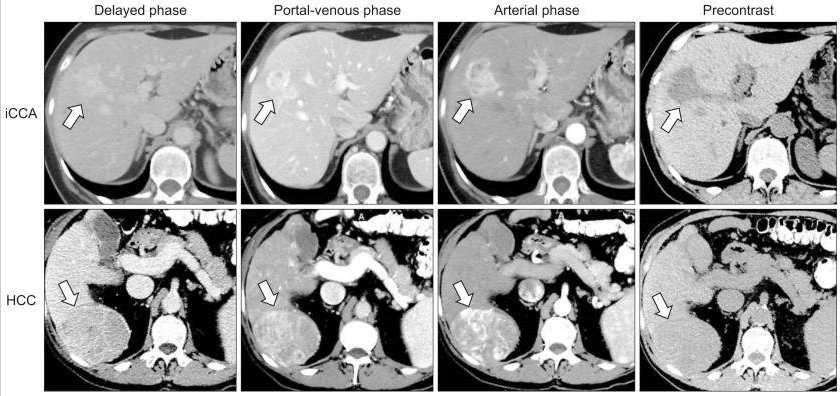

Uma vez diagnosticada a lesão, a presença de dois exames de imagem (geralmente tomografia computadorizada e ressonância nuclear magnética) com achados típicos é considerada suficiente para o diagnóstico, não sendo necessária a realização de biópsia na maioria dos casos.

O diagnóstico geralmente é realizado por exames de imagem, sendo a ressonância nuclear magnética o exame de escolha, particularmente a colangiorressonância (RNM realizada com foco no estudo das vias biliares). A colangiopancreatografia retrógrada endoscópica (CPRE) pode ser realizada quando for necessário colher material para biópsias ou para a colocação de próteses para desobstruir e manter as vias biliares abertas.